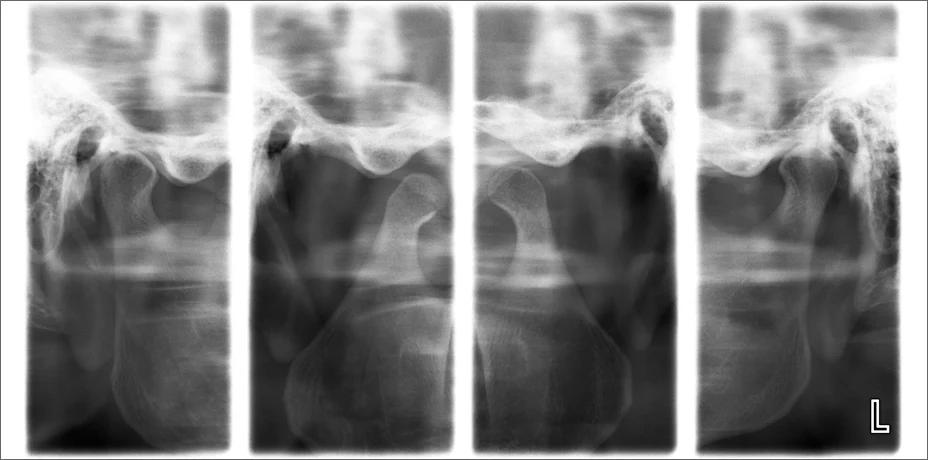

Нашият апарат позволява и рентгенография на темпоромандибуларните стави (ТМС) и синусните кухини. Облъчването е минимално.

Тези изследвания са важни при болки в ставата, ограничено отваряне на устата, щракане, както и при хронични синузити, които често са свързани със зъбен произход.